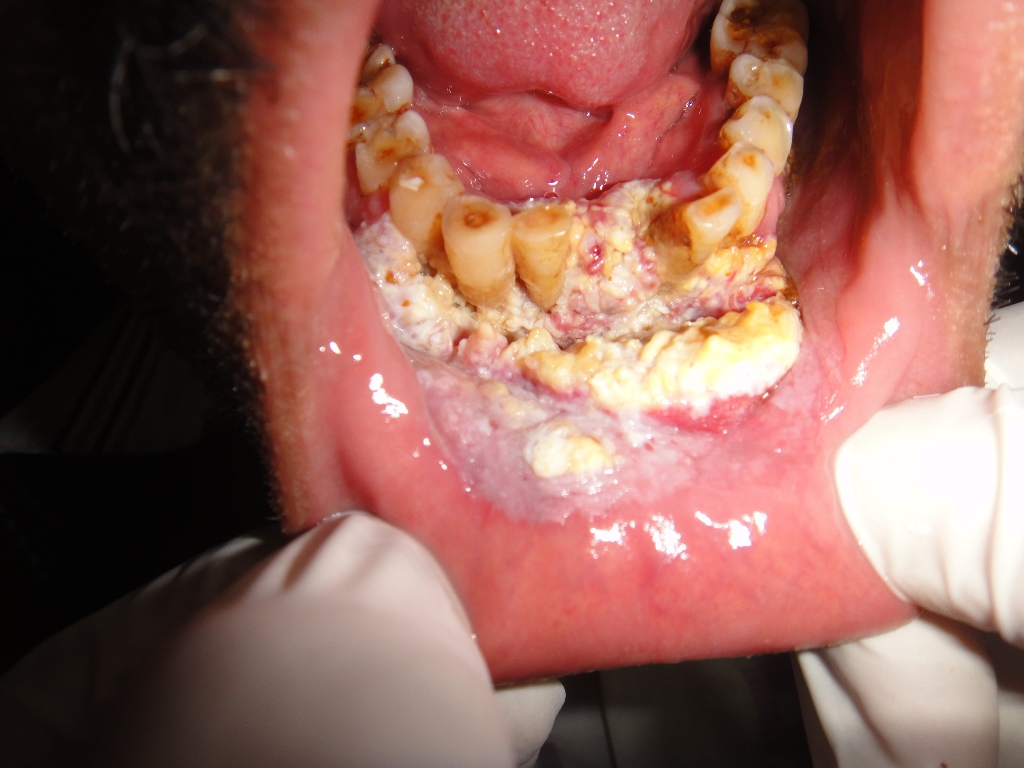

52 yrs old male suffering from right lower gingivo buccal carcinoma. Operated today for right radical neck dissection with right PM flap with right heminmandibulectomy.